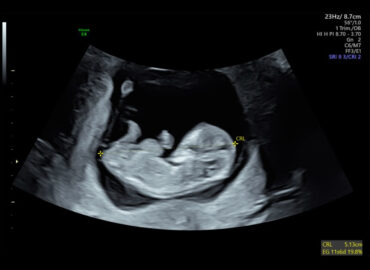

Paciente de 32 años secundigesta, nulípara AMED: Tratamiento con Isotretinoina (suspendido 2 meses previos al diagnóstico de embarazo) APP: […]